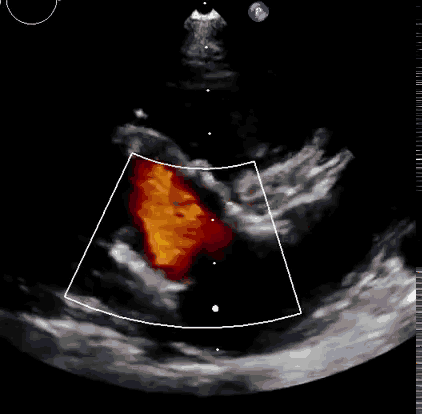

上海中山醫院葛均波院士、錢菊英院長、周達新教授、潘文志教授、潘翠珍教授、李偉教授共同完成此次臨床前研究。術后葛均波院士對Lux-Valve Plus的器械操作性能給予了高度評價,DSA和超聲影像也顯示出在本次研究中Lux-Valve Plus的安全性和有效性俱佳。

本次臨床前研究經右側頸靜脈置入LuX-Valve Plus輸送系統可調彎鞘管,在DSA及超聲引導下將人工三尖瓣瓣膜植入到原有三尖瓣位置,利用獨特的錨定技術將人工瓣膜支架可靠固定在預定的位置。

Lux-Valve是全球第一款具有我國完全自主知識產權的經導管介入三尖瓣置換系統,利用前瓣夾持及室間隔錨定的復合方式進行瓣膜裝置的固定,不依賴瓣環徑向支撐力,同時采用自適應復合裙邊材料,有效的貼合密封柔軟的三尖瓣瓣環,針對于三尖瓣返流的患者有優異的療效。Lux-Valve Plus采用全新的經血管輸送系統,經頸靜脈入路創傷更小,可以進一步降低手術風險。相信在后期正式臨床研究開展中,Lux-Valve Plus必定會為更多的三尖瓣反流患者帶來福音。